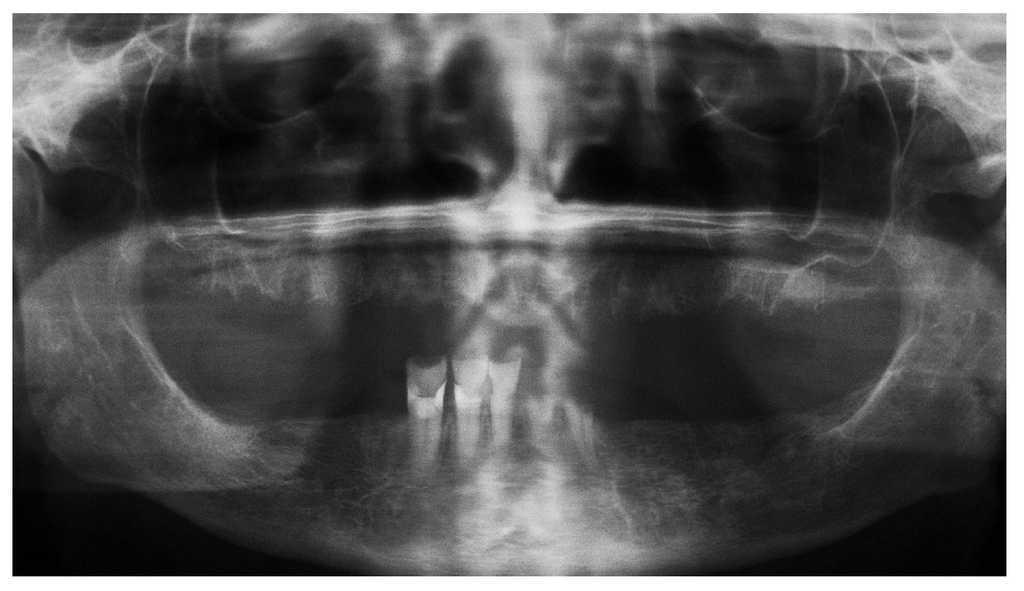

Figura 3a. Radiografía panorámica de una paciente de 68 años con un carcinoma de mama con metástasis óseas. Desde el año 2002 la paciente es tratada periódicamente con bifosfonatos intravenosos (Aredia). En 2006, el odontólogo de la paciente extrajo parte de los dientes de la mandíbula y la totalidad de los dientes superiores. La curación evolucionó de forma tórpida, sobre todo en la mandíbula, y provocó precozmente una dehiscencia de tejidos blandos. Así y todo, esta paciente no nos fue remitida hasta al cabo de 1 año.

Figura 4a. Radiografía panorámica de un paciente de 64 años con carcinoma de próstata metastatizado. El paciente recibe tratamiento con bifosfonatos intravenosos (Zometa) desde 2005. El paciente es portador de una prótesis total desde hace varios años. En junio de 2007 experimentó una sensación de presión debajo de la prótesis en la región mandibular izquierda, que no desapareció después de varios intentos de ajuste por el protésico dental. En julio de 2007, el odontólogo de cabecera remitió al paciente al servicio de urgencias de nuestra clínica.